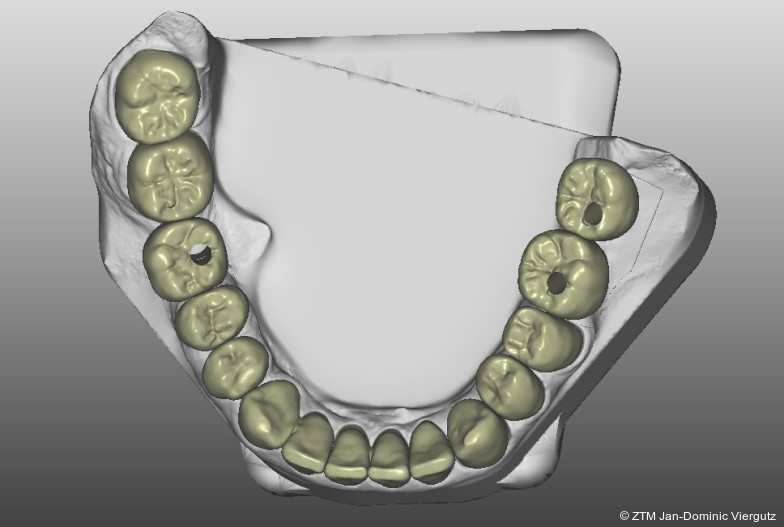

Am folgenden Tag erfolgte eine erneute Konsultation, bei der gemeinsam mit dem Patienten Form und Farbe des Provisoriums evaluiert wurden. Die Zahnfarbe wurde auf VITA A2 angepasst, mit den übrigen Parametern zeigte sich der Patient zufrieden. Diese individuelle Abstimmung garantierte, dass alle relevanten Informationen für die definitive Versorgung vorlagen.Im nächsten Schritt wurden sämtliche digitalen Scans miteinander gematcht (Modellier, Zirkonzahn) und die Modelle via 3D-Druck (Cadspeed) erstellt. Die CAD-Konstruktion der insgesamt 28 Kronen erfolgte mit Prettau 3 Dispersive Multilayer-Zirkon (Zirkonzahn). Für die Frontzähne wurde eine keramische Verblendung (Initial Zr-FS, GC) gewählt, während die Seitenzähne monolithisch mit Prettau 3 Dispersive (Zirkonzahn) gestaltet wurden. Die Bisslage der definitiven Versorgung wurde statisch an die mit der Michigan-Schiene ermittelte Position angepasst. Für die funktionelle Gestaltung der Restauration wurden Gruppenführung und „freedom in centric“ gewählt, um eine physiologische Belastung der Kiefergelenke sicherzustellen.